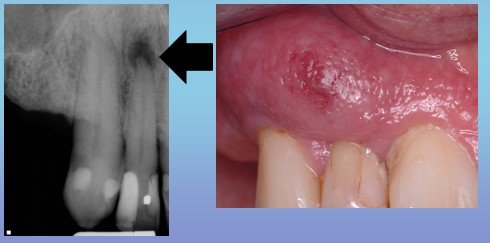

牙 如果任由疾病的发展,牙髓腔内的炎性物质无法顺利排出,就会通过根尖处的小孔挤进牙根尖周围,引起根尖周围发炎,简称“根尖周炎”。越来越多的渗出物在根尖处聚集,压力不断增大,患者在感受疼痛的同时,也会觉得牙齿有“伸长感”。

齿 好可怕!听说过,有了“伸长感”都不敢闭嘴,似乎一闭嘴别的牙没碰到,就先碰到这个牙齿了。那该如何治疗呢?

牙 医生多会在牙齿的表面磨个洞,使里面的过大的“压力”释放出来,疼痛就会得到明显的缓解。对了齿哥,你听说过有坐飞机牙痛的吗?

牙 不错。在高压氧舱中,由于压力的改变,也可引起气压性牙痛。所以需要接受高压氧舱治疗的朋友一定要对自己的口腔状况有所了解,避免气压性牙痛的发生。(图5 6)